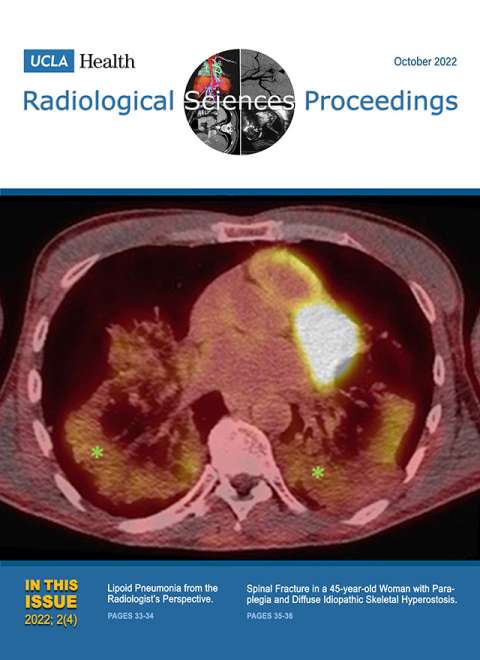

July 2022

Volume 2, Issue 3

- Inguinal Hernia Containing the Fallopian Tube and the Ovary in a Premature Infant: A Case Report

- Imaging Intertrochanteric Extension of Greater Trochanteric Fracture in a 59-year-old Man: A Case Report

- Congenital Stenosis of the Duodenum due to Duodenal Web in a Neonate: A Case Report